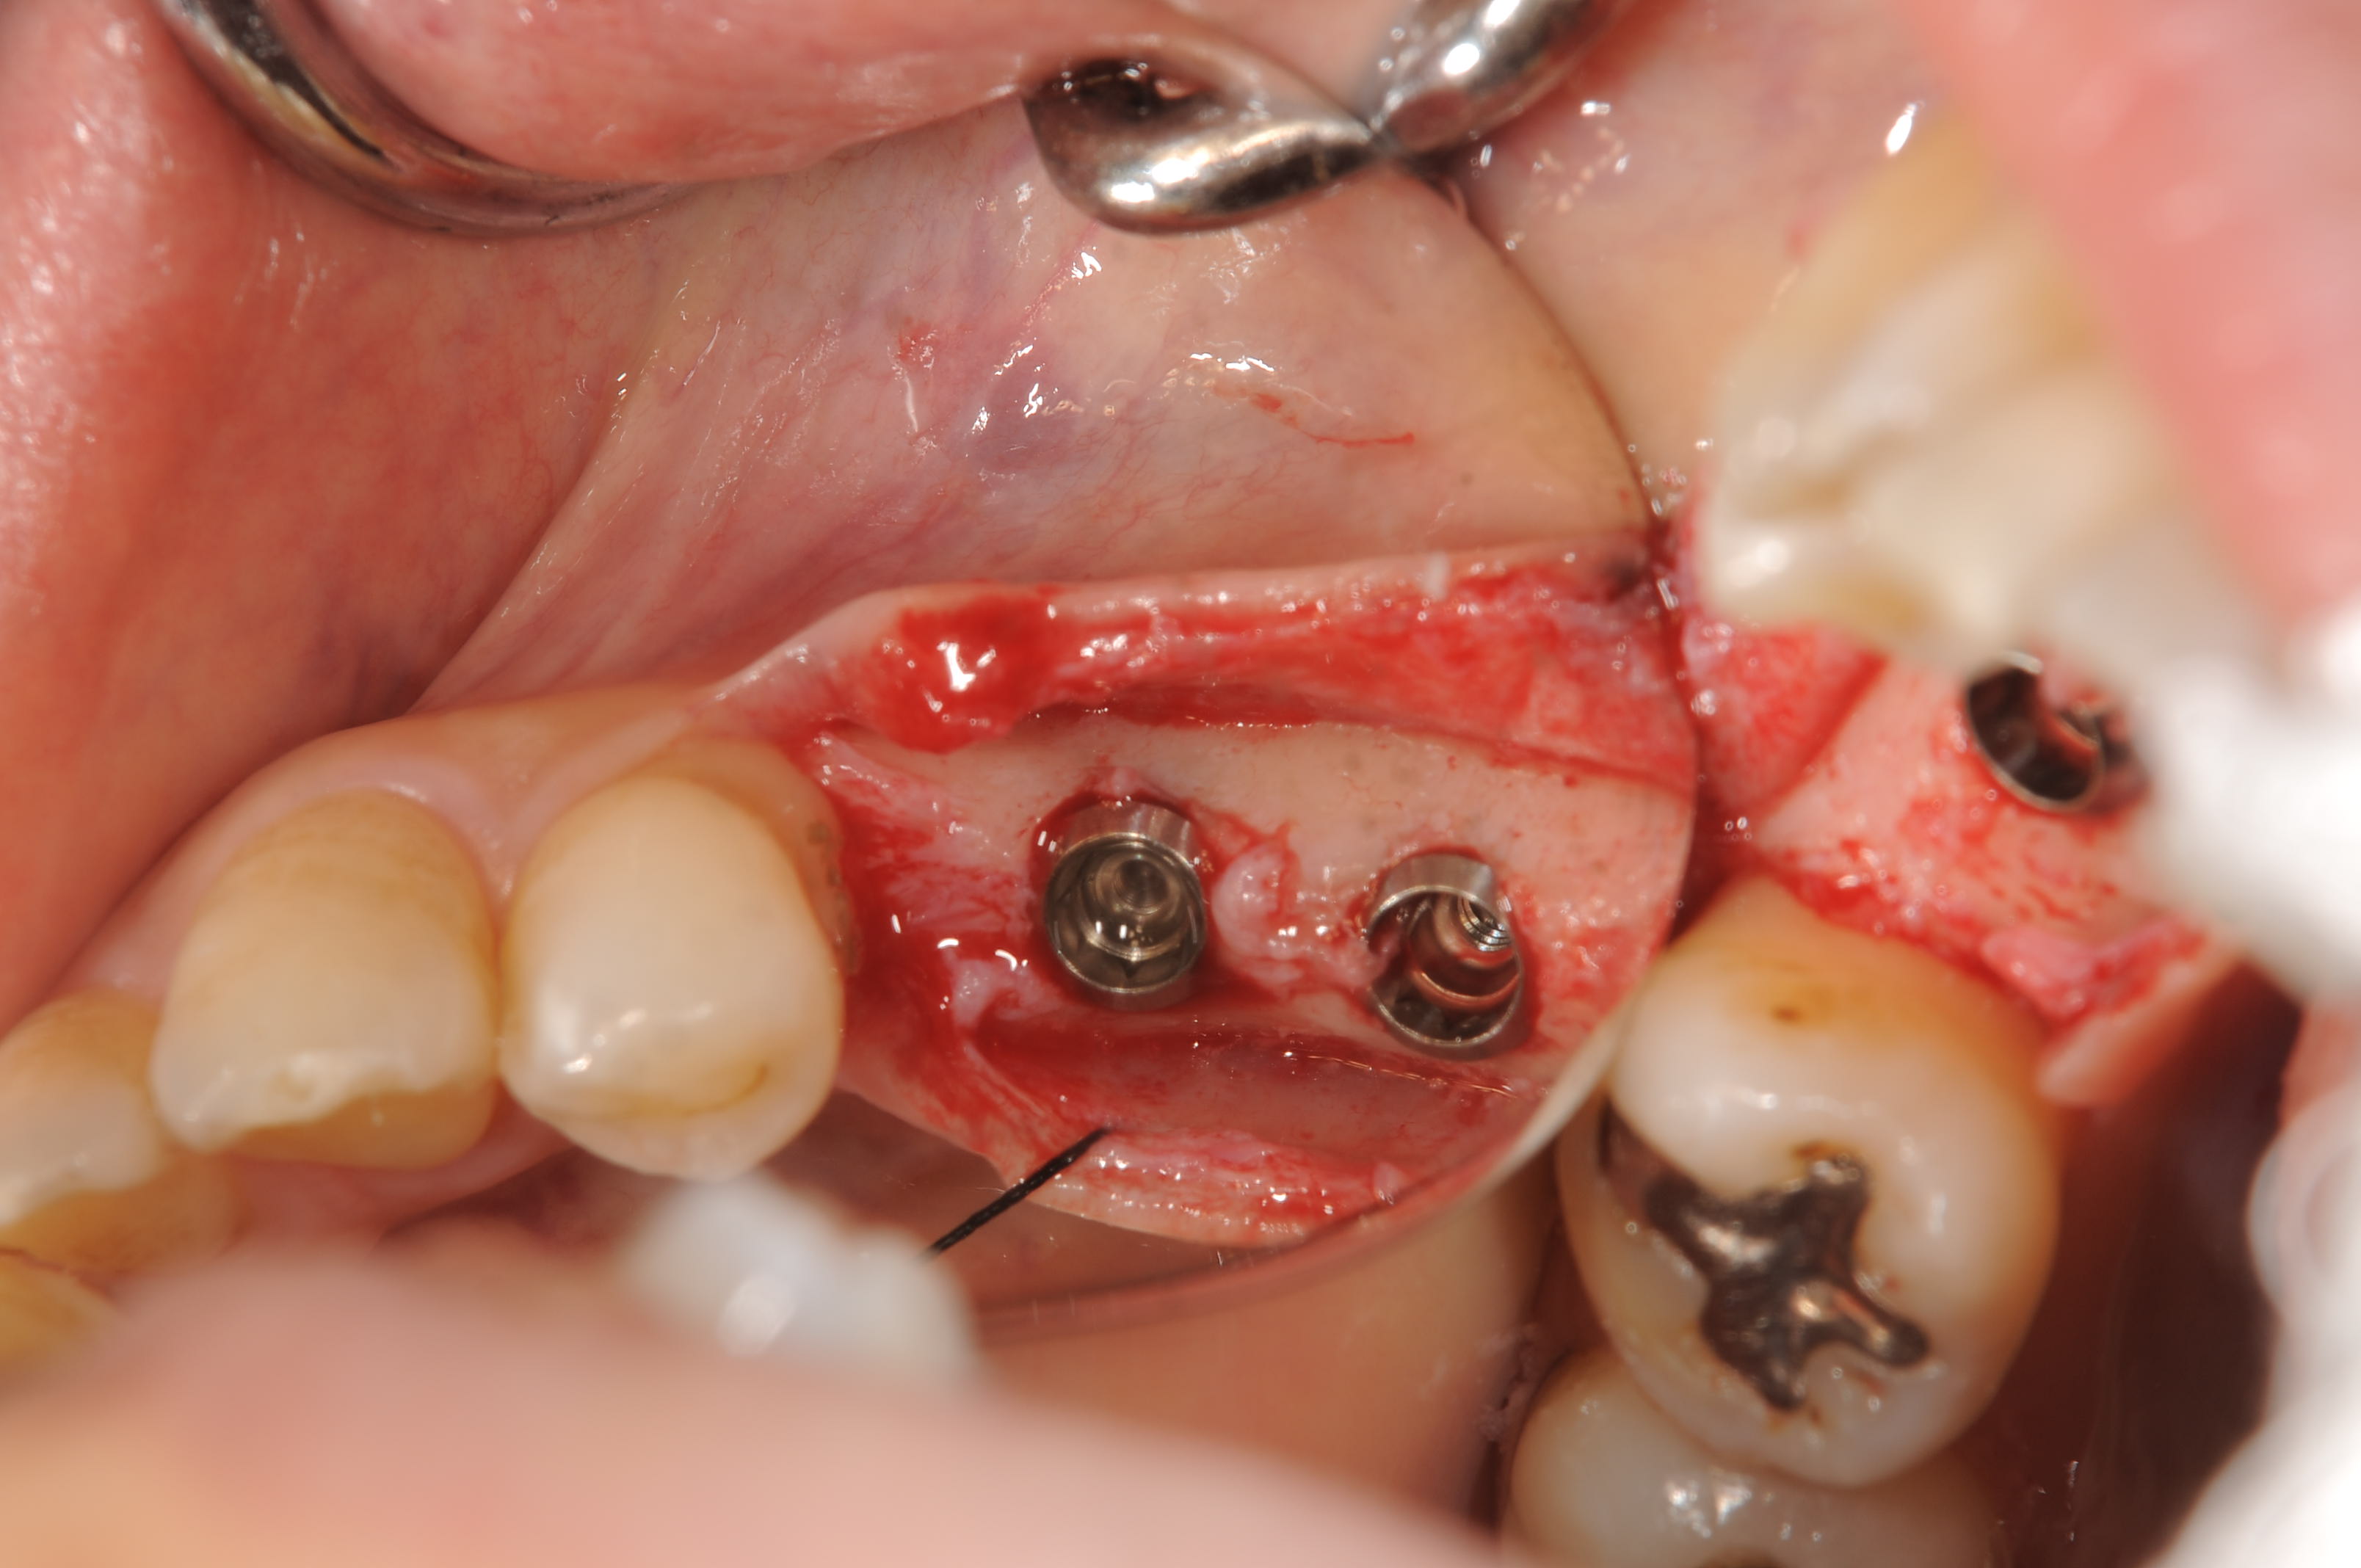

今日の症例は、下顎56番部位の成熟側埋入で特に問題のないケースです。

サイブロンプロEXのRN11mmを2本埋入しました。

初期固定は35N以上取れていますが、即時加重はせずに待時加重を行います。

埋入深度は近遠心で骨縁下1mm、頬舌側で骨縁です。歯肉の厚みと使用するアバットメントのことまで考えて埋入深度を決定します。